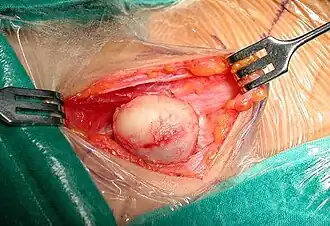

Surgery of a suprasternal epidermoid cyst, showing a smooth surface

Surgery of a suprasternal epidermoid cyst, showing a smooth surface -